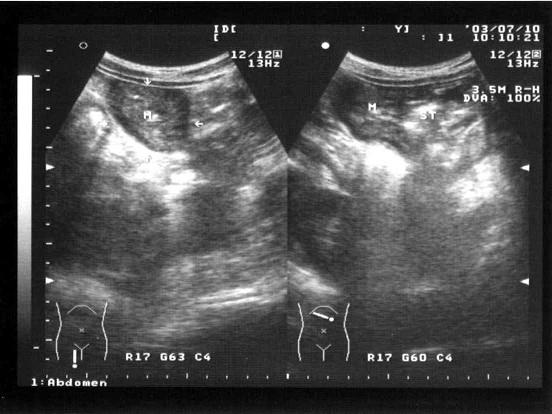

问题 患者,消瘦,于左上腹触及一包块,超声见一大小5×7cm的呈假肾征的光团,如图所示,考虑为?(?)

选项 A.胰腺癌 B.胆囊癌 C.肝癌 D.胃癌 E.左肾癌

答案 D